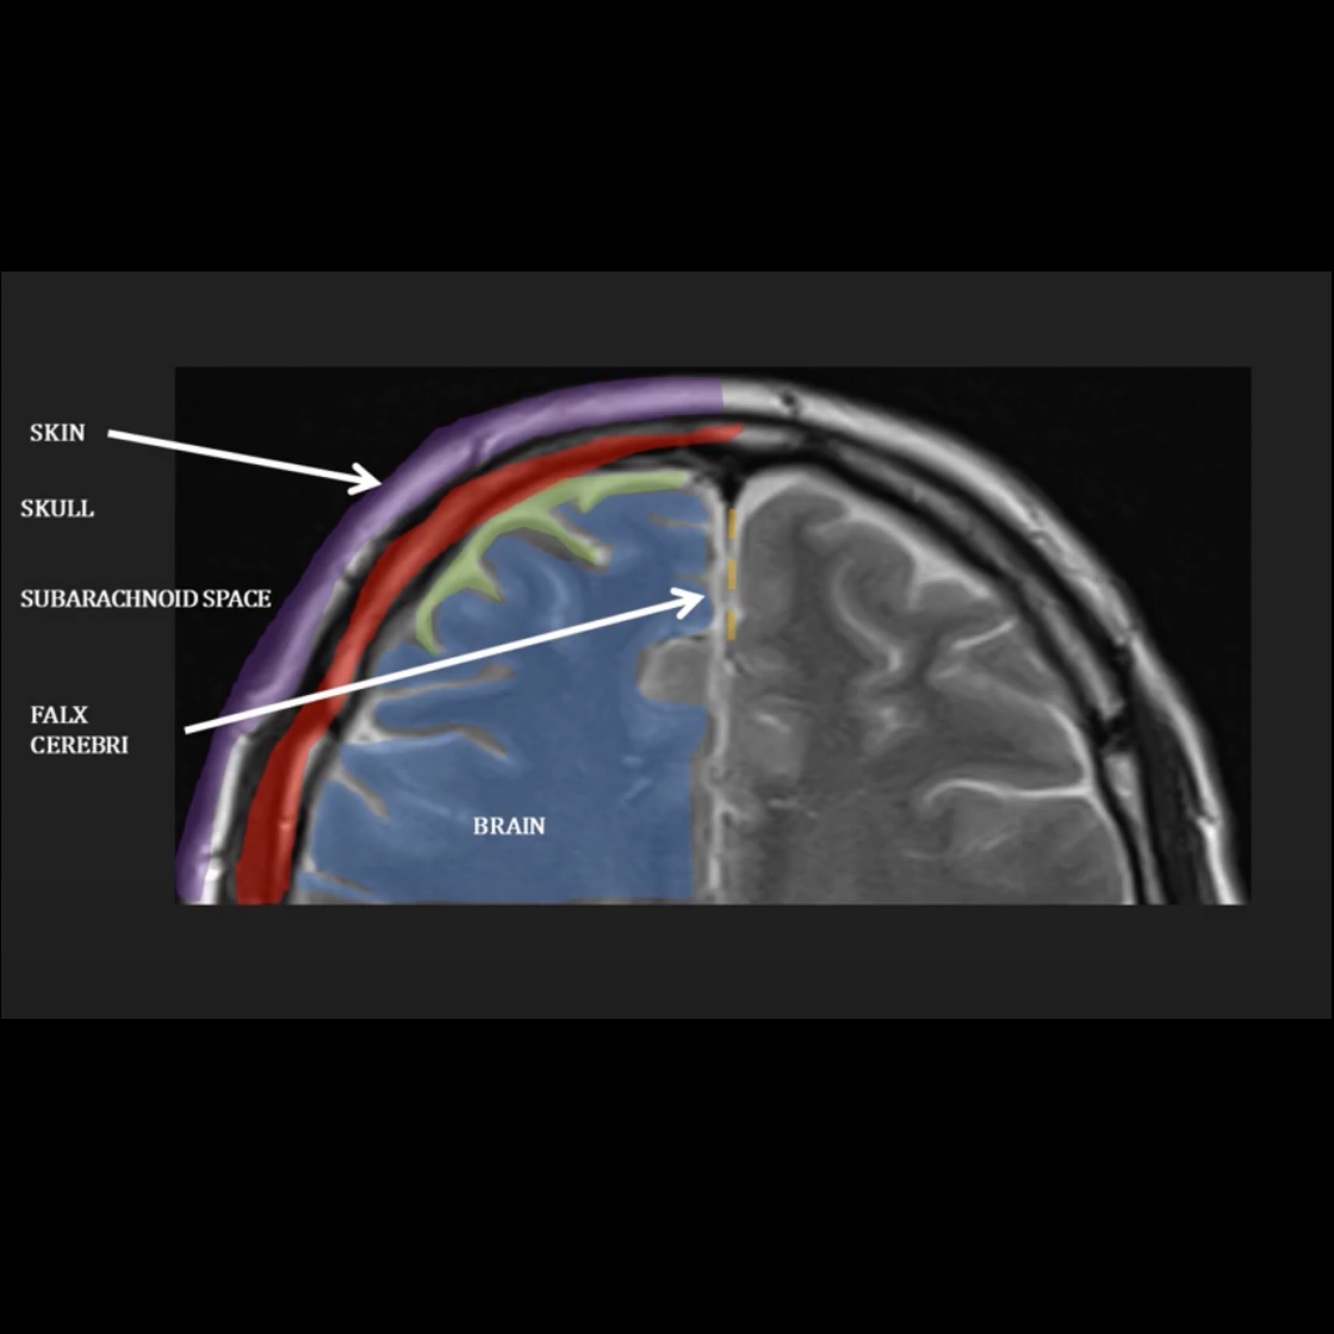

Q

Identify the relevant anatomy on this scan?